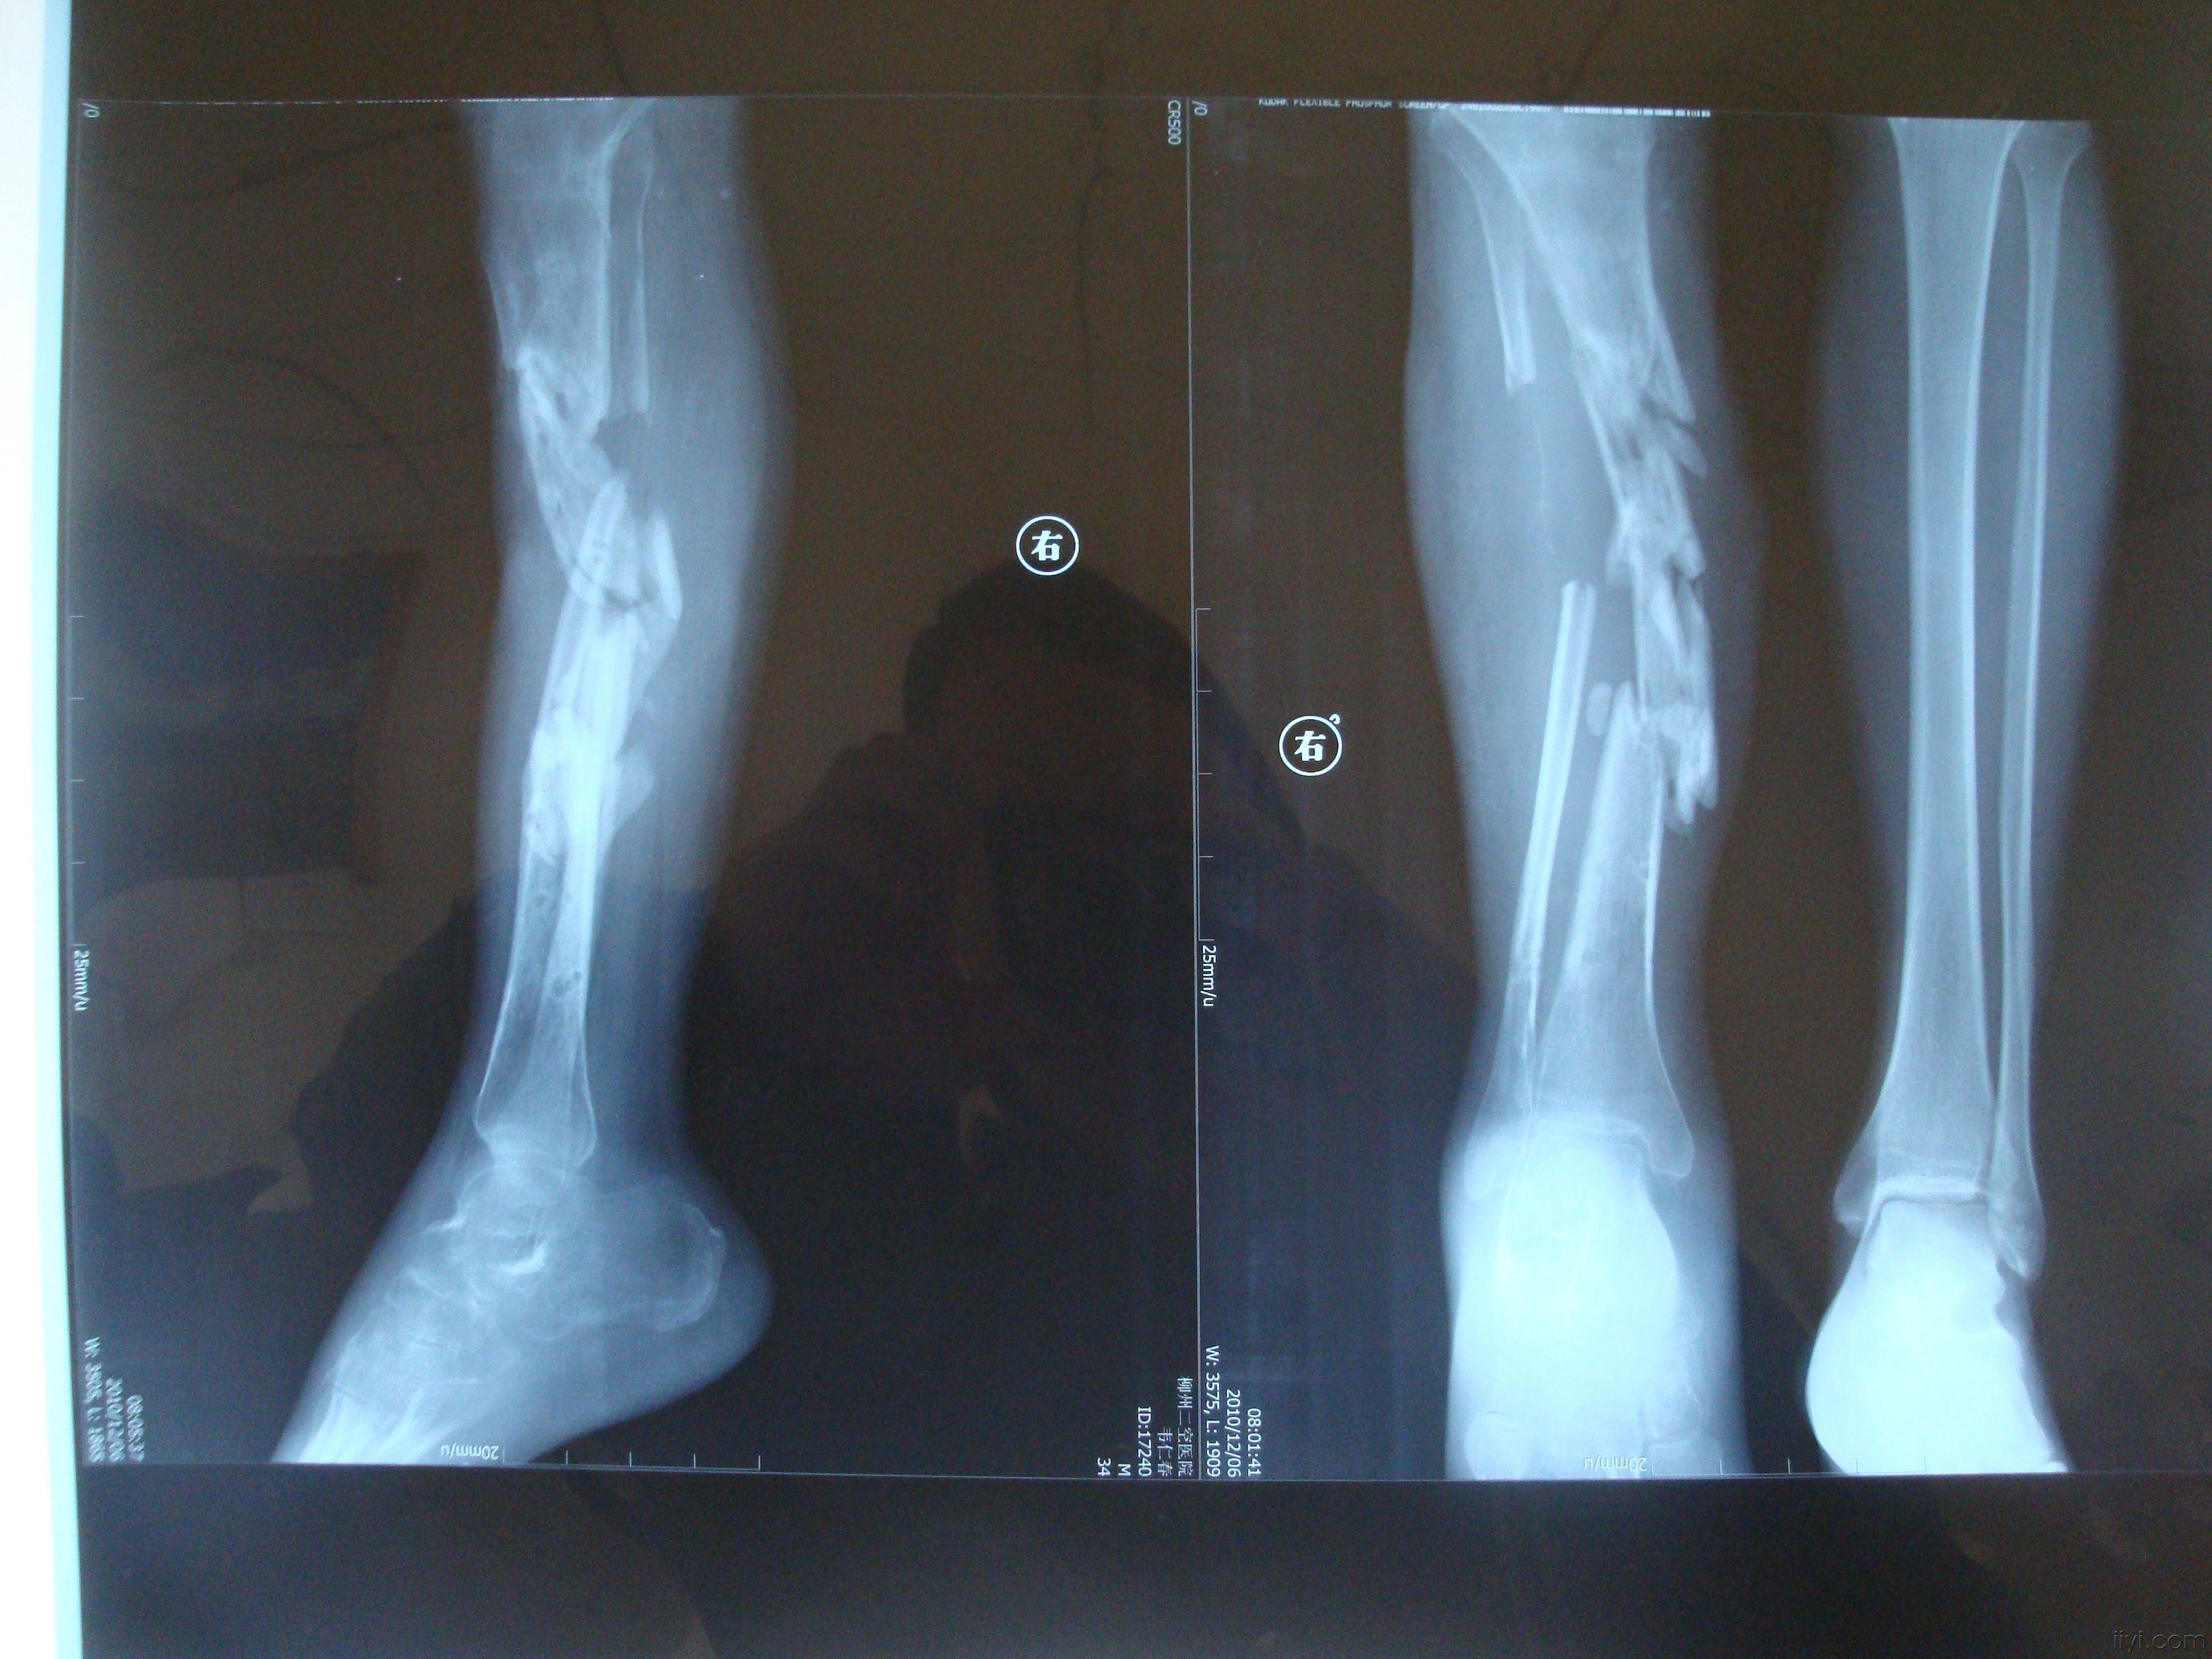

右胫骨骨不连

图片尺寸640x853